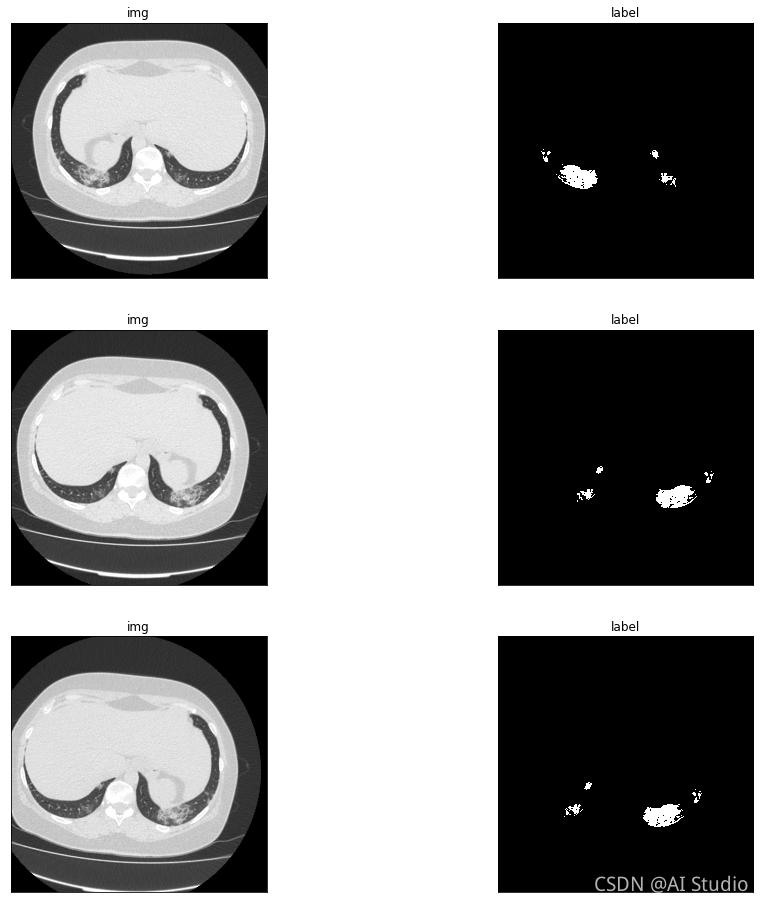

#预览经过数据增强后的数据。

plt.figure(figsize=(16,16))

for i in range(1,6,2):

img, label = train_dataset[50]

img = np.transpose(img, (1,2,0))

img = img*0.5 + 0.5

plt.subplot(3,2,i),plt.imshow(img,'gray'),plt.title('img'),plt.xticks([]),plt.yticks([])

plt.subplot(3,2,i+1),plt.imshow(label,'gray'),plt.title('label'),plt.xticks([]),plt.yticks([])

plt.show